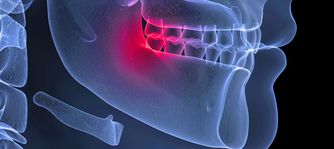

Oral surgeon, Dr. Rogers manages a wide variety of problems relating to the mouth, teeth and facial regions. Dr. Rogers practices a full scope of oral and maxillofacial surgery with expertise ranging from dental implant surgery and wisdom tooth removal. This also includes techniques designed to rebuild bone structure with minimal surgical intervention and optimal patient comfort. We can also diagnose and treat facial pain, facial injuries, and fractures.